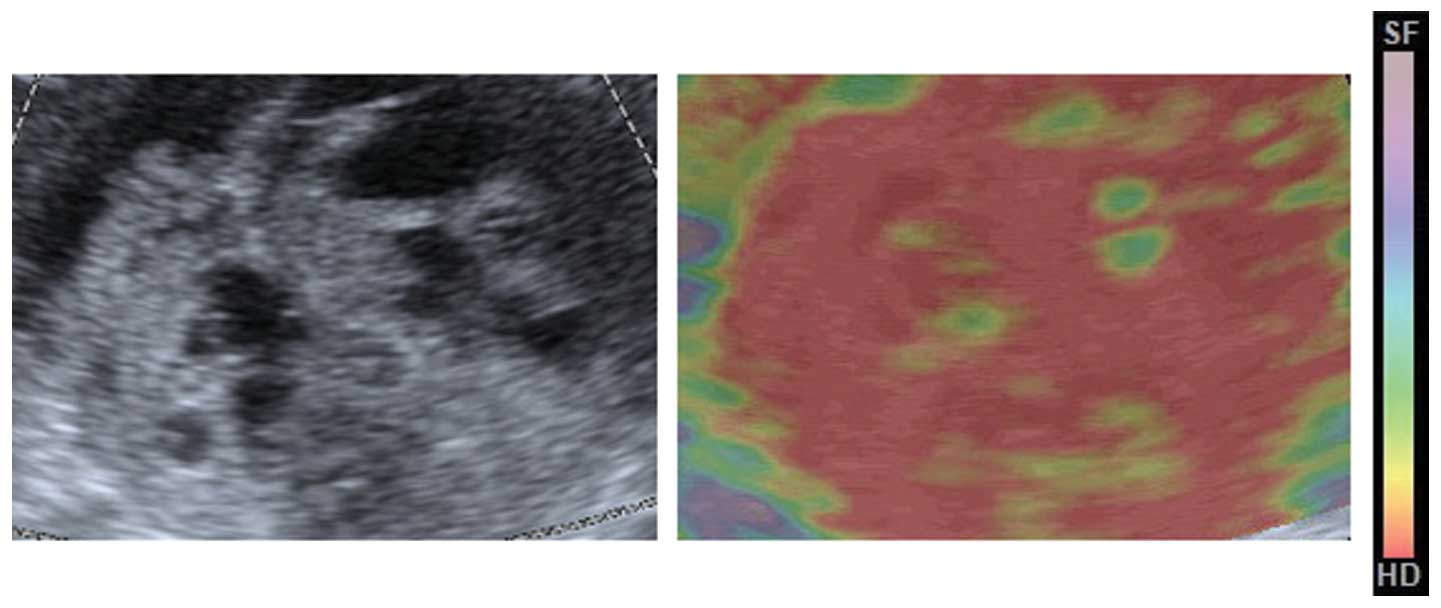

All procedures were performed by a single radiologist with 10 years of experience in transvaginal and transabdominal sonography who had specialized in elastography for the last three years. All patients underwent imaging with an Acuson S2000 system (Siemens Medical Solutions, Mountain View, CA, USA) using a transvaginal 7-MHz probe and a transabdominal 4–5-MHz probe. First, with conventional transvaginal and transabdominal sonography, the tumor was located and assessed for its size and overall sonographic appearance. Three vessels were measured and the mean pulsatility and resistive indices were calculated. The section of the ovarian tumor with the largest solid component was selected for analysis. In each scanning plane selected for documentation with conventional sonography, transabdominal elastography was also performed immediately after acquisition of the conventional grayscale sonogram. Next, the real-time elastogram and grayscale sonogram were displayed simultaneously in the dual mode. The region of interest in the elastogram was set to include sufficient surrounding mass tissue. The tissue elasticity information was superimposed over the sonogram and displayed in color, with green indicating medium tissue stiffness, red indicating hard tissue and blue indicating soft tissue, as confirmed by previously published studies that had used the Acuson S2000 system (9).

The median elasticity score for the pre-NACT lesions on the four-point scale was 2, and the score for the post-NACT lesions was 4. The distributions of the elasticity scores for pre- are post-NACT are shown in Table III. Of the pre-NACT lesions, 79.2% were scored as 1 or 2, and 20.8% were scored as 3. Of the post-NACT lesions, 66.7% were scored as 3 and 4, and 33.3% were scored as 1 and 2 (Figs. 1 and 2). Cases of post-NACT with scores of 3 and 4 had a higher optimal cytoreduction rate than the cases with scores of 1 and 2 (93.8 vs 25.0%, respectively; P<0.001). When the post-NACT elasticity scores of 3 and 4 were used for the prediction of optimal cytoreduction, elastography had 88.2% sensitivity, 85.7% specificity, a 93.8% PPV, a 75.0% NPV and 87.5% accuracy.

The present study demonstrated that elastography may be useful in predicting the outcome of neoadjuvant therapy in patients with advanced HGSC. In our prior study (9), two different types of serous ovarian cancer were evaluated that showed different stiffness ranges on elastography. A tendency for HGSC to be less stiff than low-grade serous carcinoma (LGSC) was identified, which may be elucidated by the fact that the predominantly solid tissue of HGSC developed necrosis rapidly. Conversely, LGSC grew relatively slowly so that its solid lesions were less flexible and more stiff (9). Recent studies have confirmed that chemotherapy based on platinum for patients with the p53 mutation has higher sensitivity, in contrast to previous theories (16,17). Indeed, owing to the loss of the capability to repair DNA, rapidly proliferating cells of HGSC are more sensitive to platinum (16). Chemotherapy has been found to control the development of cell necrosis in force, and the stiffness of HGSC post-NACT is likely to develop toward that of LGSC (17). As a result, the mean elasticity score of the pre-NACT lesions was lower than that of the post-NACT lesions in the present study. This indicated that techniques with functions rather than anatomy imaging may provide improved precision in monitoring response, as functional changes are predicted to develop prior to morphological changes.